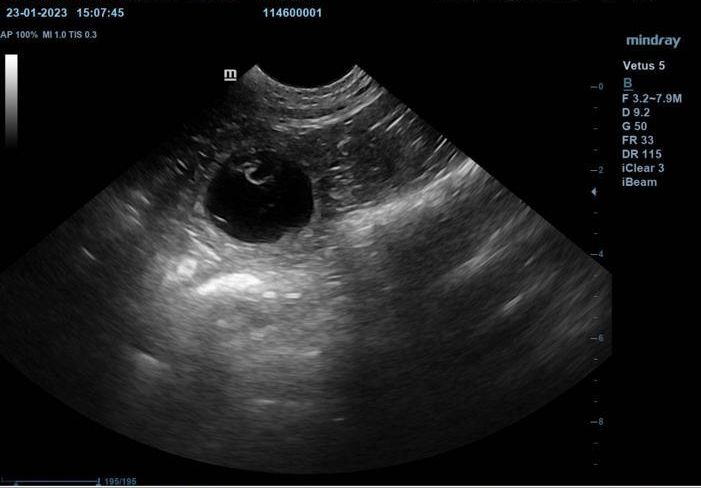

Ajari deckte Bo am 27. und 28. Dezember. Am 25. Januar 2023 hatten wir es "weiß in schwarz": Ajari wird Papa! Man konnte auf dem Ultraschall viele Fruchtanlagen sehen und wir fieberten den kleinen Berliner Ende Februar entgegen.